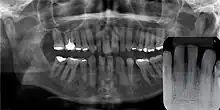

Gingival cyst of adult (arrow)

Panoramal radiograph of GCA. Inset: no evidence of bone involvement.

Gingival cyst of adult is a rare condition. The incidence is less than 0.5%. It is formed from the rests of dental lamina.[11] It is found in the soft tissues on the buccal and labial portions of the jaw. It usually occurs on the facial gingiva as a single small flesh colored swelling, sometimes with a bluish hue due to the cystic fluid. Sometimes, it may occur in cluster, either unilaterally or bilaterally or on the lingual surface of the alveolar process. It is most commonly seen in the canine and premolar regions of the mandible, and are sometimes confused with lateral periodontal cysts.[12] It is not normally problematic, but when it grows larger, it can cause some discomfort. It can be removed by simple surgical excision. They are developed late in life, generally up to the sixth decade of age.[1]